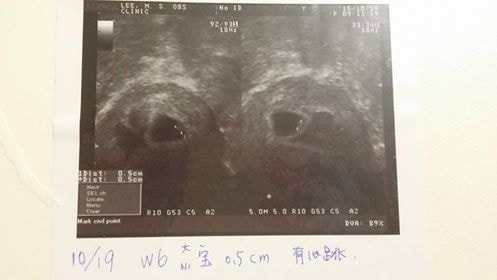

20151019-48kg

6W產檢

今天看到雙寶的心跳,一閃一閃的,像是告訴麻麻有很健康的乖乖在肚子裡待著。

護士阿姨說,現在有0.5公分大了!成長速度很好很正常。

只是旁邊還有一個小血塊還沒消掉,讓我有點擔心。希望血塊能趕快消失,給雙寶足夠的空間可以平安長大。